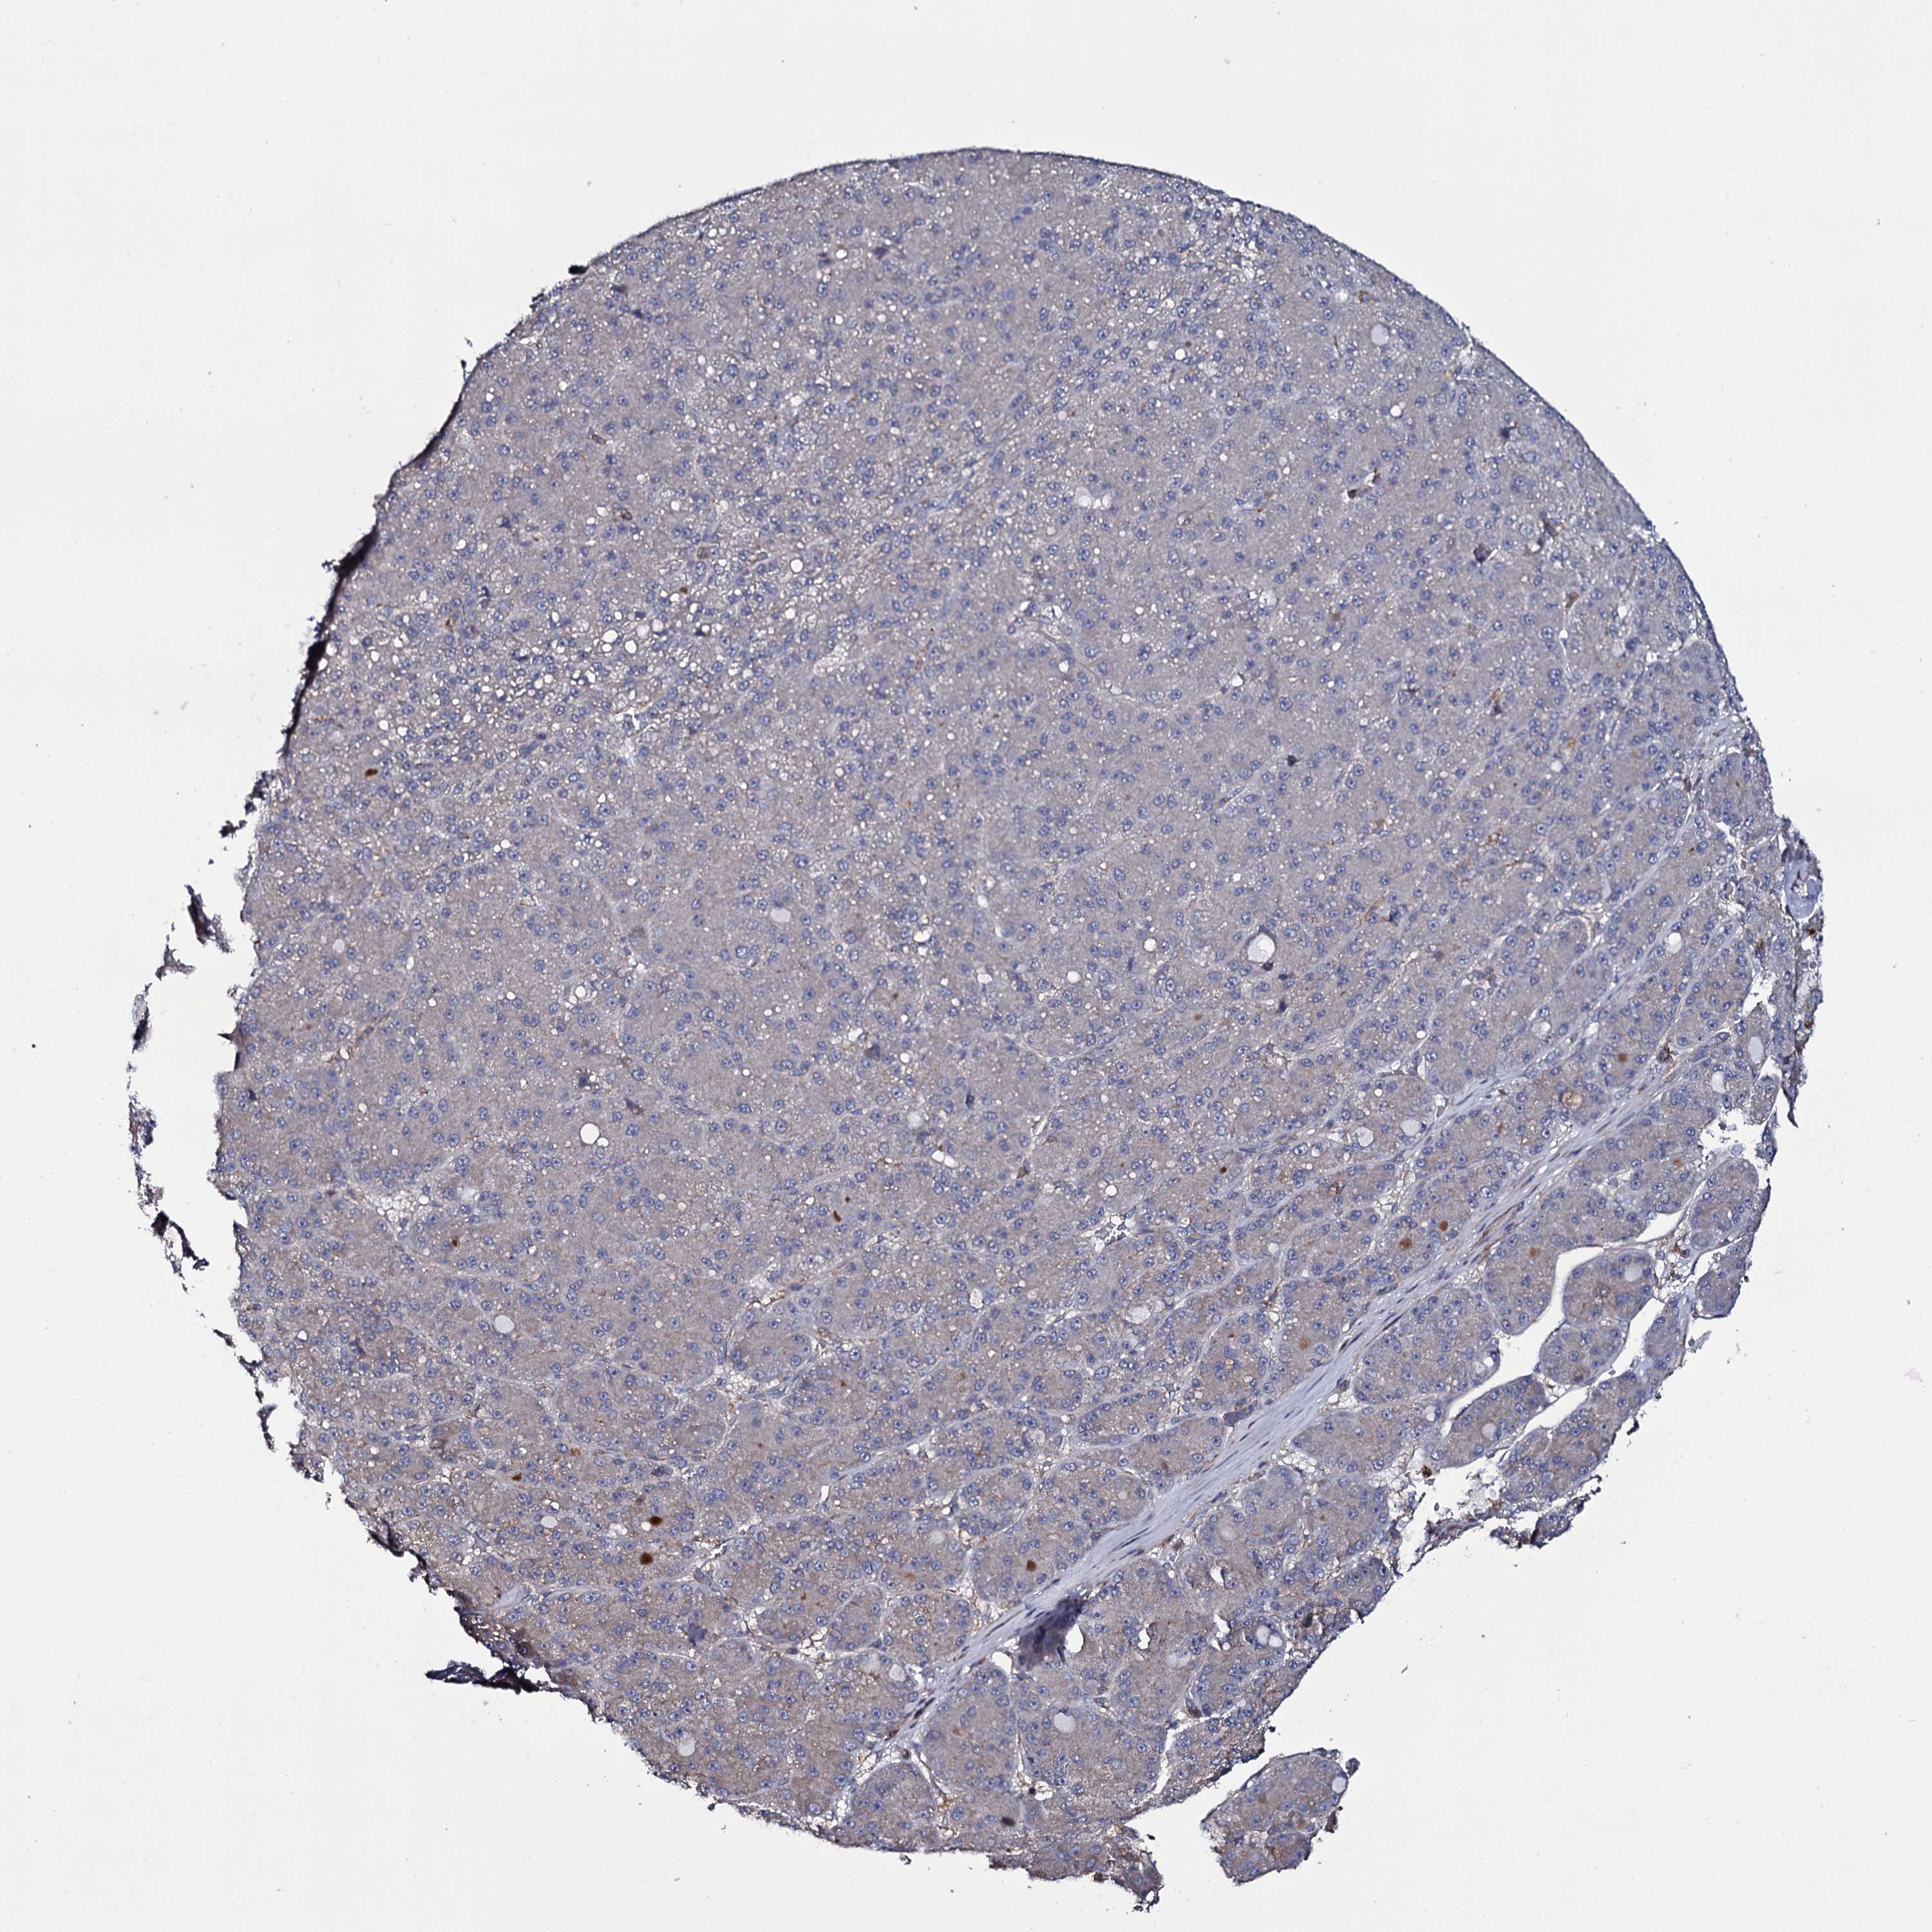

LIVER CANCER - Protein expressioni

A mouse-over function shows sample information and annotation data. Click on an image to view it in a full screen mode. Samples can be filtered based on level of antibody staining by selecting one or several of the following categories: high, medium, low and not detected. The assay and annotation is described here.

Note that samples used for immunohistochemistry by the Human Protein Atlas do not correspond to samples in the TCGA dataset.

Antibody stainingi

Antibody staining in the annotated cell types in the current human tissue is reported as not detected, low, medium, or high, based on conventional immunohistochemistry profiling in selected tissues. This score is based on the combination of the staining intensity and fraction of stained cells.

Each image is clickable and will lead to virtual microscopy that enables deeper exploration of all samples and also displays staining intensity scores, fraction scores and subcellular localization as well as patient and tissue information for each sample.

Antibody HPA039806

Antibody HPA040369

Staining

High

Medium

Low

Not detected

Intensity

Strong

Moderate

Weak

Negative

Quantity

>75%

75%-25%

<25%

None

Location

Nuclear

Cytoplasmic/membranous

Cytoplasmic/membranous,nuclear

Cholangiocarcinoma

Carcinoma, Hepatocellular, NOS